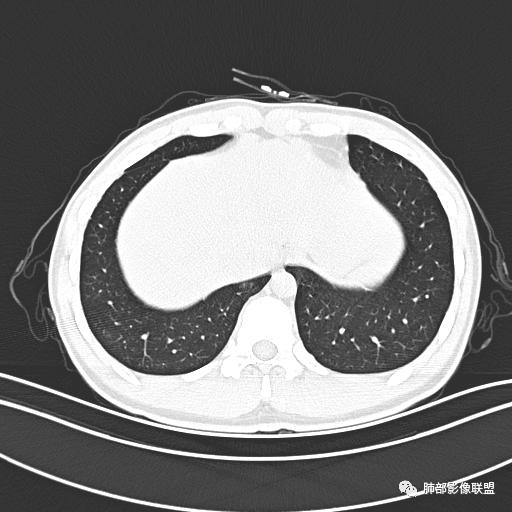

小强:青年,发热,皮疹;双肺散在结节,周围磨玻璃,点晕征,疱疹病毒感染,鉴别荚膜组织胞浆菌,结核。 大雄:青年,急性起病,发热伴全身皮疹2天,抗病毒治疗体温有下降。双肺随机分布大小不等类圆结节,“点晕征”。考虑水痘-疱疹病毒(VZV)血播询问接触史,查体皮疹分布以及形态基本可诊断。 王开金江津中心医院呼吸科:青年男性,起病急,病程短,以发热,皮疹为首发症状,感染指标以单核细胞升高为主,胸部ct双肺多发结界,周围有晕,点晕表现,随机分布,同意於老师意见,水痘疱疹病毒血流感染累及肺。 王秀仙:双肺多发大小不等结节,周围有晕,边缘模糊,呈点晕征表现。青年,急性起病,发热伴全身皮疹2天,抗病毒治疗体温有下降。考虑疱疹病毒。鉴别荚膜组织胞浆菌。 傅昌瑜:19岁男性,发热、全身皮疹2天,单核细胞增高,双肺多发结节,结节边缘见边界不清磨玻璃影。点晕征+发热、全身皮疹+单核细胞增高——考虑水痘-带状疱疹病毒肺炎。 一切∮随缘:年轻男性,发热,皮疹两天,实验室,CRP,PCT增高,影像:双肺多发散在磨玻璃结节,边界欠清,大小不等,呈点晕征改变,以血管束周围分布为主,局部血管束略增粗,其它无明显改变,考虑:1:病毒性肺炎(水痘疱疹病毒?不知道皮肤有无改变)2:真菌(组织胞浆菌,血管侵袭性肺曲霉)3:GPA4:寄生虫(实验室没有看到嗜酸细胞增高) 赵山河:双肺散在结节,周围有晕,边缘模糊,呈点晕征表现。青年,急性起病,发热伴全身皮疹2天,抗病毒治疗体温有下降。考虑水痘—疱疹病毒感染。洪桥爱:青年男性,发热、皮疹2天,伴瘙痒,皮疹于面部首发,之后进展至全身,虽然没有对皮疹进行描述,但是从出疹时间及皮疹进展情况,伴瘙痒,应该就是个水痘患者;CT提示双肺随机分布结节影,部分结节伴有边界不清晕征,考虑水痘血播肺。 刘强:年轻男性,急性起病,皮疹,发热,抗感染治疗体温下降,说明有效。影像表现为散在点晕征,感染类疾病谱(疱疹病毒,真菌,结核),结合年龄,皮肤皮疹,考虑水痘-疱疹病毒性肺炎。 小兜:男性,19岁,发热皮疹两天,颜面部至全身,CRP,降钙素及单核增高。CT示双肺散在小结节,周围伴磨玻璃影,点晕征,考虑为水痘-带状疱疹病毒(varicella-zoster virus,VZV)肺炎 必有路:青年,皮疹+发热+“点晕征”→水痘-疱疹病毒(VZV) 许慧良:青年男性患者,发热、皮疹2天,体温最高38.5℃,第3天皮疹扩展至全身,伴瘙痒,胸部CT:双肺多发随机分布的小结节,结节周边见边界模糊的晕征,考虑水痘病毒感染流心明智:男,19,急性起病,发热伴全身皮疹2天。出疹顺序头→全身,抗病毒有效。胸部CT:两肺多发大小不等类圆形实性小结节影,随机分布,结节周围环绕GGO,边界模糊,呈点晕征。出疹特点是关键,未提示。考虑:血播病毒性肺炎,水痘-疱疹病毒?麻疹?鉴别荚膜组织胞浆菌、TB、血管炎、寄生虫等。 浪迹天涯:病灶多为5-10mm大小结节,结节周围可见磨玻璃样的晕环,常多发,可分布于肺内任何区域,考虑水痘—带状疱疹病肺炎如果短时间内有新的一个区域浸润,更加能说明,